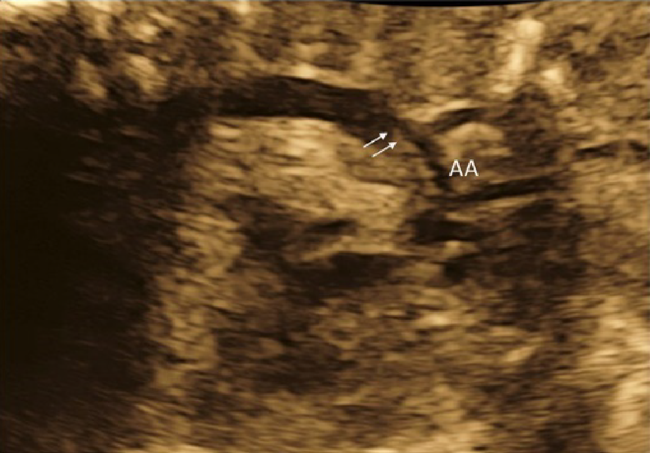

How to decide and choose treatments are multifactorial, as explained below.

1. Gestational Age

i) If an immature baby can cope with morbid or detrimental circumstances after birth, early delivery followed by postnatal treatment of arrhythmia is preferred, though practical arrangement would depend on the facility of the institution. In postnatal treatment, various antiarrhythmic drugs can be administered without endangering the maternal body. A standard electrocardiogram is available, and immediate treatment, namely direct current shock, intravenous administration of adenosine triphosphate, etc. can take place. The cesarean section is an option of choice to deliver patients with sustained tachycardia as it is difficult to monitor fetal heart rate during vaginal delivery. An alternative would be transplacental treatment with digoxin, which is relatively safe for the mother, and vaginal delivery when the fetus resume sinus rhythm. Risks of antiarrhythmic agents to the maternal body should be fully explained to the family.